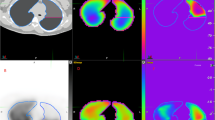

The experimental setup is shown in Fig. 2. The HIFU transducer (H102, Sonic Concepts, Bothell, WA, USA) with a sideways adjusted imaging probe and PCD detector was immerged in the saline filled tank. The transducer operates at 1,1 MHz, it has an outer diameter of 64 mm and a central opening of 20 mm resulting in an F number of 0,98. The transducer was mounted onto a manual adjustable 3D motion stage, and was driven by a RF power amplifier (RF-Source, Athens, Greece) through the manufacture supplied 50 Ohm impedance matching. Sonographic imaging and HIFU were not synchronised. Signals from the PCD were sampled using a digital oscilloscope (54645A, Agilent, Santa Clara, CA, USA) and transferred via GPIO interface to a PC for data storage. The customized PCD sensor was designed with a 550 kHz centre frequency and moderate 30% bandwidth (Smart Material, Dresden, Germany). The function generator (33120A, Agilent, Santa Clara, CA, USA) and oscilloscope were synchronised using an external trigger.

HIFU focal intensity calibration

Calibration was performed in a tank filled with degassed water. The setup contained the same HIFU transducer, amplifier and impedance matching as described above. A HIFU membrane hydrophone (HIFU-SI-03, GAMPT, Germany) was placed on a 3 axis motion stage at the focal position. This HIFU compatible hydrophone provides a large bandwidth (100 kHz–100 MHz), high dynamic range, small active element size (0,2 mm), and is able to detect pressure amplitudes up to 100 MPa [17]. The axial and lateral beam profile of the transducer and the maximum focal pressure waveform were characterised, and the hydrophone’s active element was positioned into the centre of the focal spot. The transducer input power was varied in the range of 1,5–288 W. At each power level the received hydrophone waveform was captured and deconvoluted [18] before calculating the temporal peak intensity as follows:

The resulting intensity and rarefactional pressure functions were derived using second order interpolation. The measured hydrophone amplitudes, derived rarefactional and peak positive pressures as well as the intensity values are summarized in Table 1.